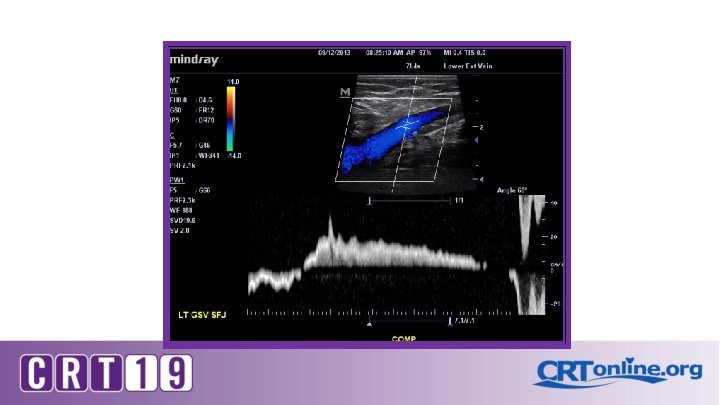

Patient position Erect, semi-erect or reverse Trendelenburg Proximal compression (or Valsalva) to elicit reflux for thigh veins Calf compression of distal veins Flow reversal duration

On Ultrasound: Grey scale , color and Doppler Compressibility Phasic flow Augmentation Perforators Reflux and its duration Vein diameters

Diagnostic testing for Venous insufficiency CVI Venous Doppler *technique* S. V. reflux >3 secs Stasis ulcer Stasis dermatitis S. V. reflux >3 secs Deep vein reflux No reflux Vein diameter Symptoms Compression stockings Ablation